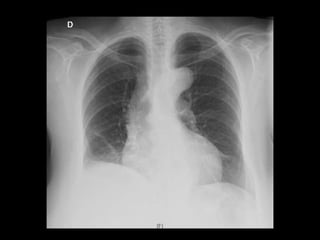

AR: Hipofonesis en base pulmonar dcha, sin otros ruidos sobreañadidos

CASO CLÍNICO EXPLORACIÓN FÍSICA AC:Rítmico, sin soplos o extratonos AR: Hipofonesis en base pulmonar dcha, sin otros ruidos sobreañadidos Abdomen: RHA +, blando, depresible, sin masas ni megalias, no doloroso Genitourinario: PPL derecha dudosa + Ap. Locomotor: Dolor a la palpación región dorso-lumbar derecha y costado derecho, que aumenta en intensidad a la inspiración profunda Extremidades: sin edemas, no signos de compromiso circulatorio, pulsos distales mantenidos